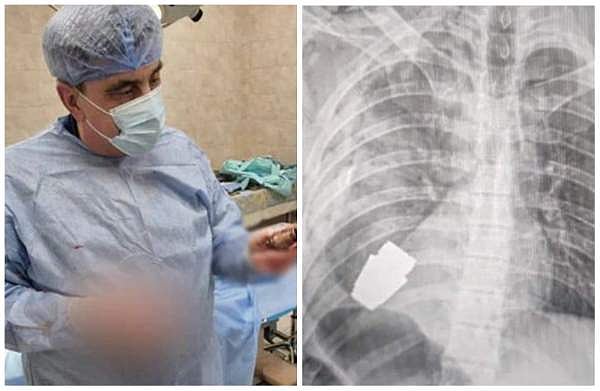

പുറത്തെടുത്ത ഗ്രനേഡുമായി ഡോക്ടര്‍, സൈനികന്റെ എക്‌സ്‌റെ

യുക്രൈന്‍ സൈനികന്റെ നെഞ്ചില്‍ തുളച്ചു കയറിയ ഗ്രനേഡ് സാഹസിക ശസ്ത്രക്രിയയിലൂടെ പുറത്തെടുത്ത് ഡോക്ടര്‍. പ്രവര്‍ത്തനം നിലച്ചിട്ടില്ലാത്ത ഗ്രനേഡ് ആണ് ഡോക്ടര്‍ പുറത്തെടുത്തത്. ബഖ്മുട് പ്രദേശത്ത് റഷ്യന്‍ ആക്രമണം ചെറുക്കുന്നതിനിടെയാണ് സൈനികന്റെ ശരീരത്തില്‍ ഗ്രനേഡ് തുളച്ചു കയറിയത്.

ഏത് നിമിഷയും പൊട്ടിത്തെറിക്കുന്ന അവസ്ഥയില്‍ ആയിരുന്നു ഗ്രനേഡ്. രണ്ട് സൈനികരുടെ സഹായത്തോടെ ആയിരുന്നു ശസ്ത്രക്രിയ. 'സൈനികന്റെ ശരീരത്തില്‍ തുളഞ്ഞു കയറിയ വിഒജി ഗ്രനേഡ് ഞങ്ങളുടെ സൈനിക ഡോക്ടര്‍ പുറത്തെടുത്തു. സൈന്യത്തിലെ ഏറ്റവും പരിചയ സമ്പന്നനായ സര്‍ജന്‍ മേജര്‍ ജനറല്‍ ആന്‍ഡ്രി വെര്‍ബ ആണ് ശസ്ത്രക്രിയ നടത്തിയത്. ഗ്രനേഡ് ഏതുനിമിഷവും പൊട്ടിത്തെറിക്കാന്‍ സാധ്യതയുണ്ടായിരുന്നു. അതിനാല്‍ ഇലക്ട്രോണിക് സഹായമില്ലാതെ ആയിരുന്നു ശസ്ത്രക്രിയ.'- യുക്രൈന്‍ സൈന്യം സാമൂഹ്യ മാധ്യമങ്ങളിലൂടെ അറിയിച്ചു.

പരിക്കേറ്റ സൈനികനെ മറ്റൊരു ആശുപത്രിയിലേക്ക് മാറ്റിയെന്നും അദ്ദേഹം സുഖം പ്രാപിച്ച് വരികയാണെന്നും യുക്രൈന്‍ സൈന്യം വ്യക്തമാക്കി. അതേസമയം, എങ്ങനെയാണ് സൈനികന്റെ ശരീരത്തില്‍ ഗ്രനേഡ് തുളച്ചതെന്നും എവിടെവെച്ചാണ് ശസ്ത്രക്രിയ നടത്തിയതെന്നും സൈന്യം വ്യക്തമാക്കിയിട്ടില്ല.